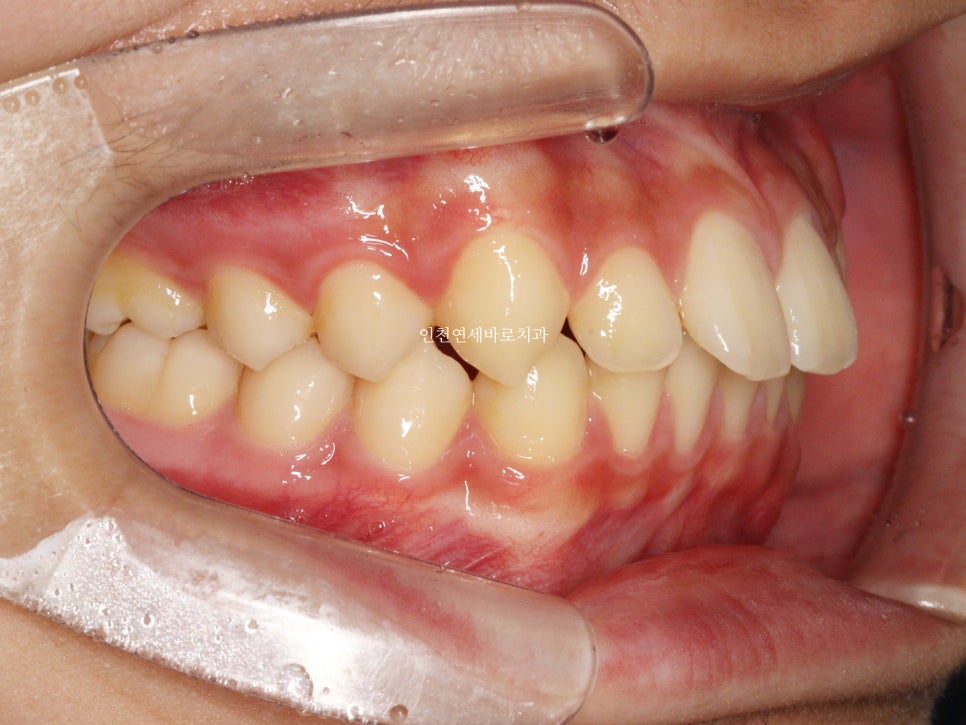

치료 전과 후 입니다.

앞니가 후방이동 한것이 확인됩니다.

우리는 부분교정을 한것이 아니라 간단한 전체교정을 한것입니다.

앞니만 철사를 붙여서는 얻기 어려운 결과라고 생각합니다.